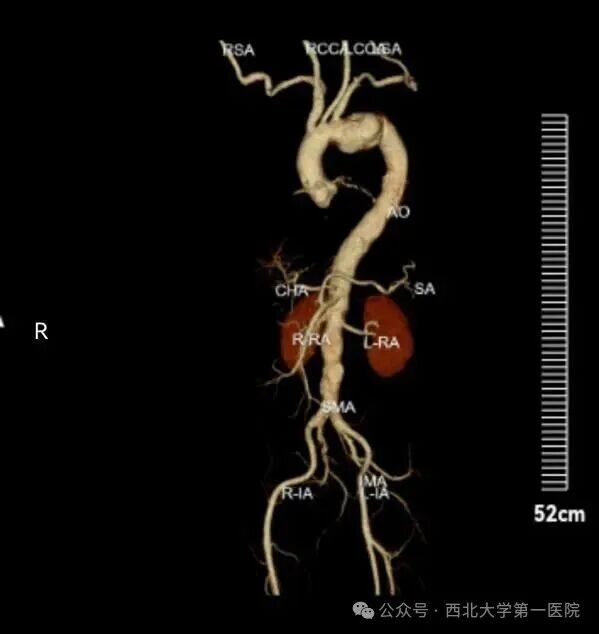

近日,西北大学第一医院介入科成功救治了一位76岁男性患者。患者因咳嗽3天就诊于呼吸与危重症医学科门诊,完善胸部CT平扫后提示主动脉弓动脉瘤,医生随即建议进一步行主动脉CTA检查,结果显示:主动脉弓动脉瘤伴壁内血肿,同时合并主动脉硬化、多发钙化斑及软斑。

经介入科副主任医师张海福会诊评估,患者动脉瘤体积较大,且有长期高血压病史,胸主动脉瘤破裂引发致死性大出血的风险极高,必须通过手术干预,才能彻底解除这场生命危机。